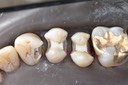

Photos of Clinical Operations

Mentors: Drs. Randy Allan, Greg Card, Peter Kearney

Clubs #44 and #50 joint meeting